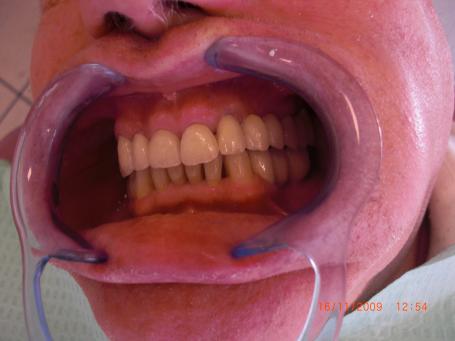

6°)Pose du bridge céramique définitif.

On peut voir sur cette photo les couronnes dentaires sur les implants posés 2 mois auparavant. Ces 2 mois correspondent à un temps de cicatrisation osseuse pour que l'os réalise une soudure autour de l'implant dentaire.